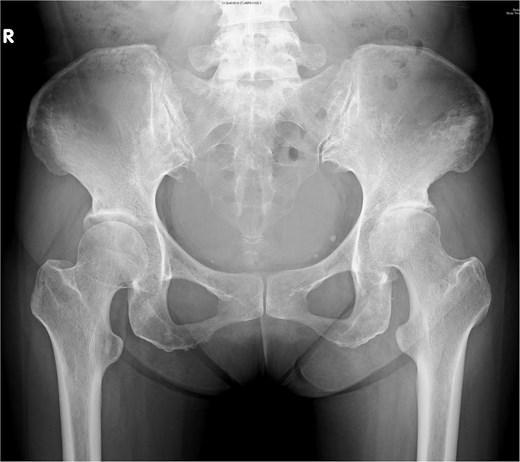

A 44-year-old female, with a medical history of invasive ductal carcinoma of the breast with multiple sites of metastasis (brain, pulmonary, liver, and bone), presented to the outpatient clinic with progressive intractable pain over the left inguinal area in the preceding month. Radiography revealed symmetrical joint space narrowing of the left hip joint (Fig. 1). Computed tomography (CT)revealed a well-lobulated cystic lesion within the left psoas muscle, extending caudally into the hip joint (Fig. 2a and b). The serum C-reactive protein (CRP) level was 55.04 mg/dl at admission. Due to the inaccessibility of CT-guided percutaneous abscess drainage, she underwent a scheduled surgical debridement of the psoas abscess. Resection arthroplasty with polymethylmethacrylate hip spacer implantation was planned simultaneously.

Computed tomography of a 44-year-old female demonstrating (a) a psoas abscess and (b) hip septic arthritis. Postdebridement surgery and resection arthroplasty, the abscess completely resolved (c, d).

A bacterial culture of the pus yielded Staphylococcus aureus. After debridement surgery and parental use of sensitive antimicrobial agents, the CRP levels decreased over time (Fig. 4). A repeat CT scan revealed a completely diminished abscess within the iliac fossa (Fig. 3c and d). The patient underwent total hip arthroplasty three months after the first surgery. However, she died 2 months later because of multiple organ failure caused by cancer metastasis.